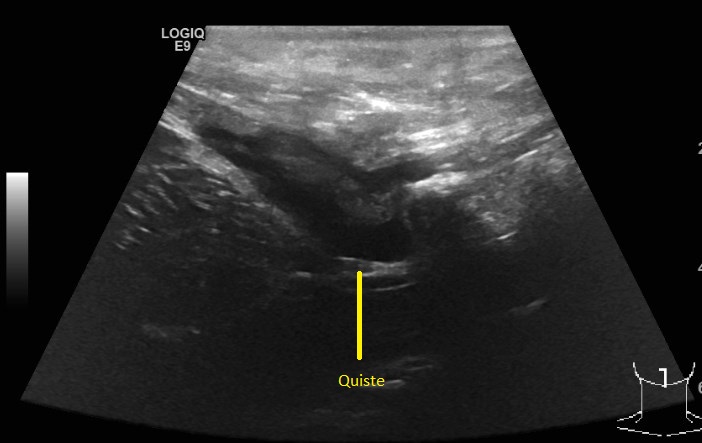

El 13 de diciembre tuve mi primer control fuera del hospital, previo a la cita, me saqué una tomografía y el ultrasonido. El doctor quería ver si el quiste redujo su tamaño, y así fue pero me pidió seguir con la medicina para el cerebro y el vendaje, del acné me dijo que iba a tardar algunos meses, lo mismo que la retención de líquidos, que no me preocupara por el peso ya que en unos meses, mi cuerpo eliminaría esos kilos de manera natural. Lo que no le gusto fue mi semblante, estaba demasiado pálida y amarilla así que me mando estudios.